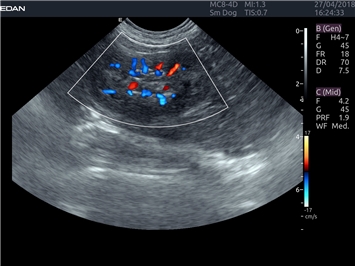

Энергетический допплер:

Да

Цветовой допплер: